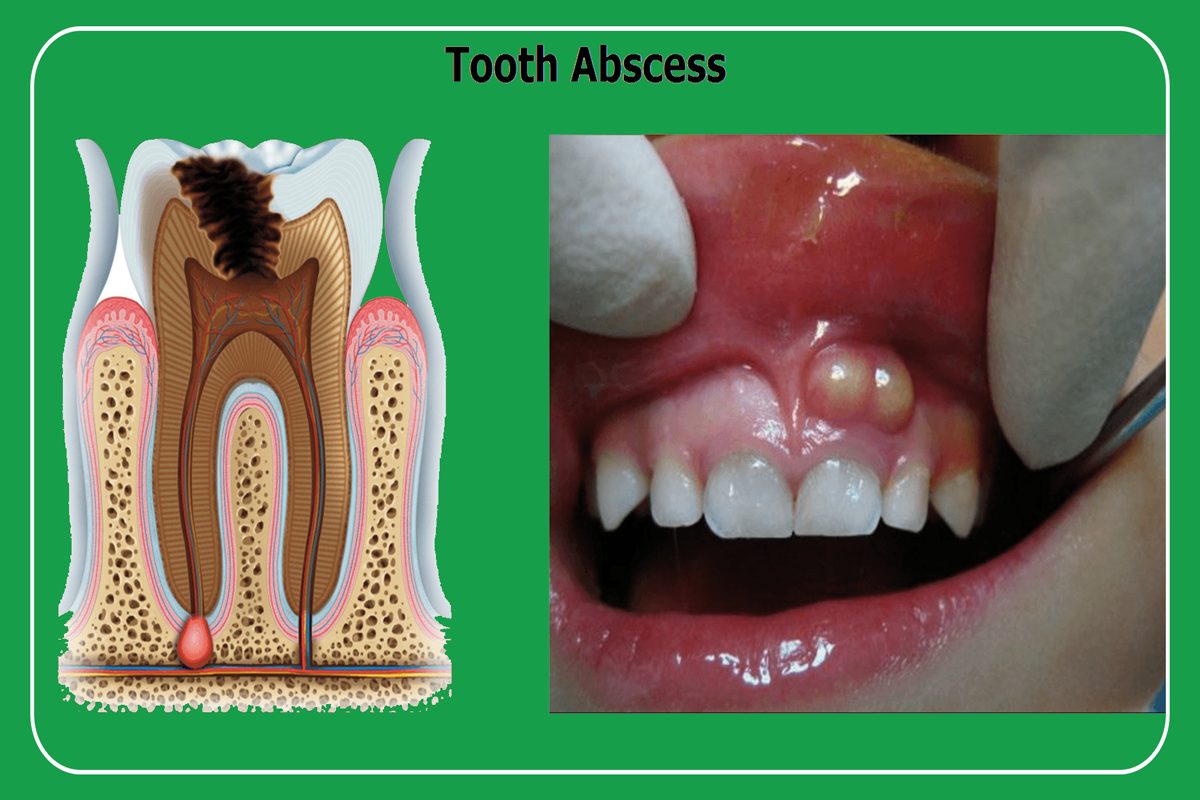

Dis Apsesi Dis Estetigi Gulus Tasarimi Dr Dt Omer Bayar